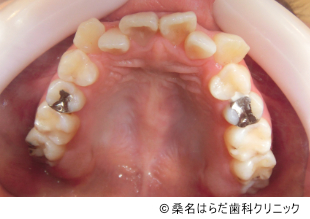

【症例4】マウスピース矯正を用いた叢生および八重歯の矯正治療

- 治療前

- 治療後

- 治療名

- マウスピース矯正を用いた叢生および八重歯の矯正治療

- 費用

- 498,000円(税込)

- 期間

- 1年9ヶ月

歯磨きのしづらさや歯周病の悩みから、歯並びを気にされて来院されました。

患者様の治療負担を減らすため、患者様と相談のうえでマウスピース矯正を選択しました。

3D光学スキャナを用いてデータをとり、治療計画と装着方法をお伝えして治療を進めました。 -

目立っていた八重歯も生えそろい、審美的・健康的な歯並びに変わりました。